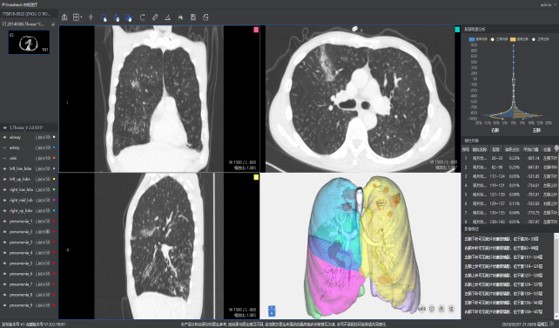

本系统是根据最新版新型冠状病毒肺炎影像学诊断指南推出的针对新型冠状病毒肺炎的轻量级辅助阅片工具。在公司原有AI辅助筛查系统的基础上,联合武汉协和医院,依据新型冠状病毒感染肺炎的影像学表征对原有AI产品做出升级,能够快速对新冠肺炎疑似病例进行诊断筛查。目前疫情在短时间内出现爆发式的就诊需求,尤其是核心地区,难以实现快速精准的诊断。本系统能够应对可能出现的大规模病例筛查,有助于及时发现潜在病例,加强防控。

快速

针对新冠肺炎的各种典型征象如:磨玻璃影(GGO)、斑片影、实性变化等,在短时间内进行快速检测,大大提高阅片效率,助力当前新冠肺炎进行大规模影像筛查。

准确

依据最新版新型冠状病毒肺炎影像学诊断指南中对CT影像诊断的要求,联手武汉协和医院,大量高质量的数据使柏视能够提供准确的处理结果。利用AI实现影像表征的自动定量化分析,通过病灶形态特征信息、密度信息等提示肺部病变;并能够自动计算出疑似概率将病例进行分级分区,方便医生逐级筛查。

多能

此次新冠肺炎传播速度快,病情发展较为迅速,早期、进展期 、重症期的影像表现有着明显区别。本系统还具备对多次检查结果进行对比分析的功能,提高诊断效率。同时,为更加方便的应对当前客户需求,系统同时具有根据医院的需求生成符合最新型冠状病毒肺炎诊断指南的结构化图文报告的功能。